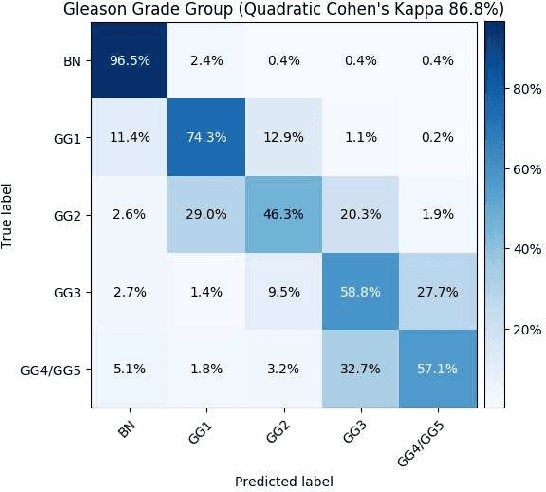

Histopathological images provide rich information for disease diagnosis. Large numbers of histopathological images have been digitized into high resolution whole slide images, opening opportunities in developing computational image analysis tools to reduce pathologists' workload and potentially improve inter- and intra- observer agreement. Most previous work on whole slide image analysis has focused on classification or segmentation of small pre-selected regions-of-interest, which requires fine-grained annotation and is non-trivial to extend for large-scale whole slide analysis. In this paper, we proposed a multi-resolution multiple instance learning model that leverages saliency maps to detect suspicious regions for fine-grained grade prediction. Instead of relying on expensive region- or pixel-level annotations, our model can be trained end-to-end with only slide-level labels. The model is developed on a large-scale prostate biopsy dataset containing 20,229 slides from 830 patients. The model achieved 92.7% accuracy, 81.8% Cohen's Kappa for benign, low grade (i.e. Grade group 1) and high grade (i.e. Grade group >= 2) prediction, an area under the receiver operating characteristic curve (AUROC) of 98.2% and an average precision (AP) of 97.4% for differentiating malignant and benign slides. The model obtained an AUROC of 99.4% and an AP of 99.8% for cancer detection on an external dataset.